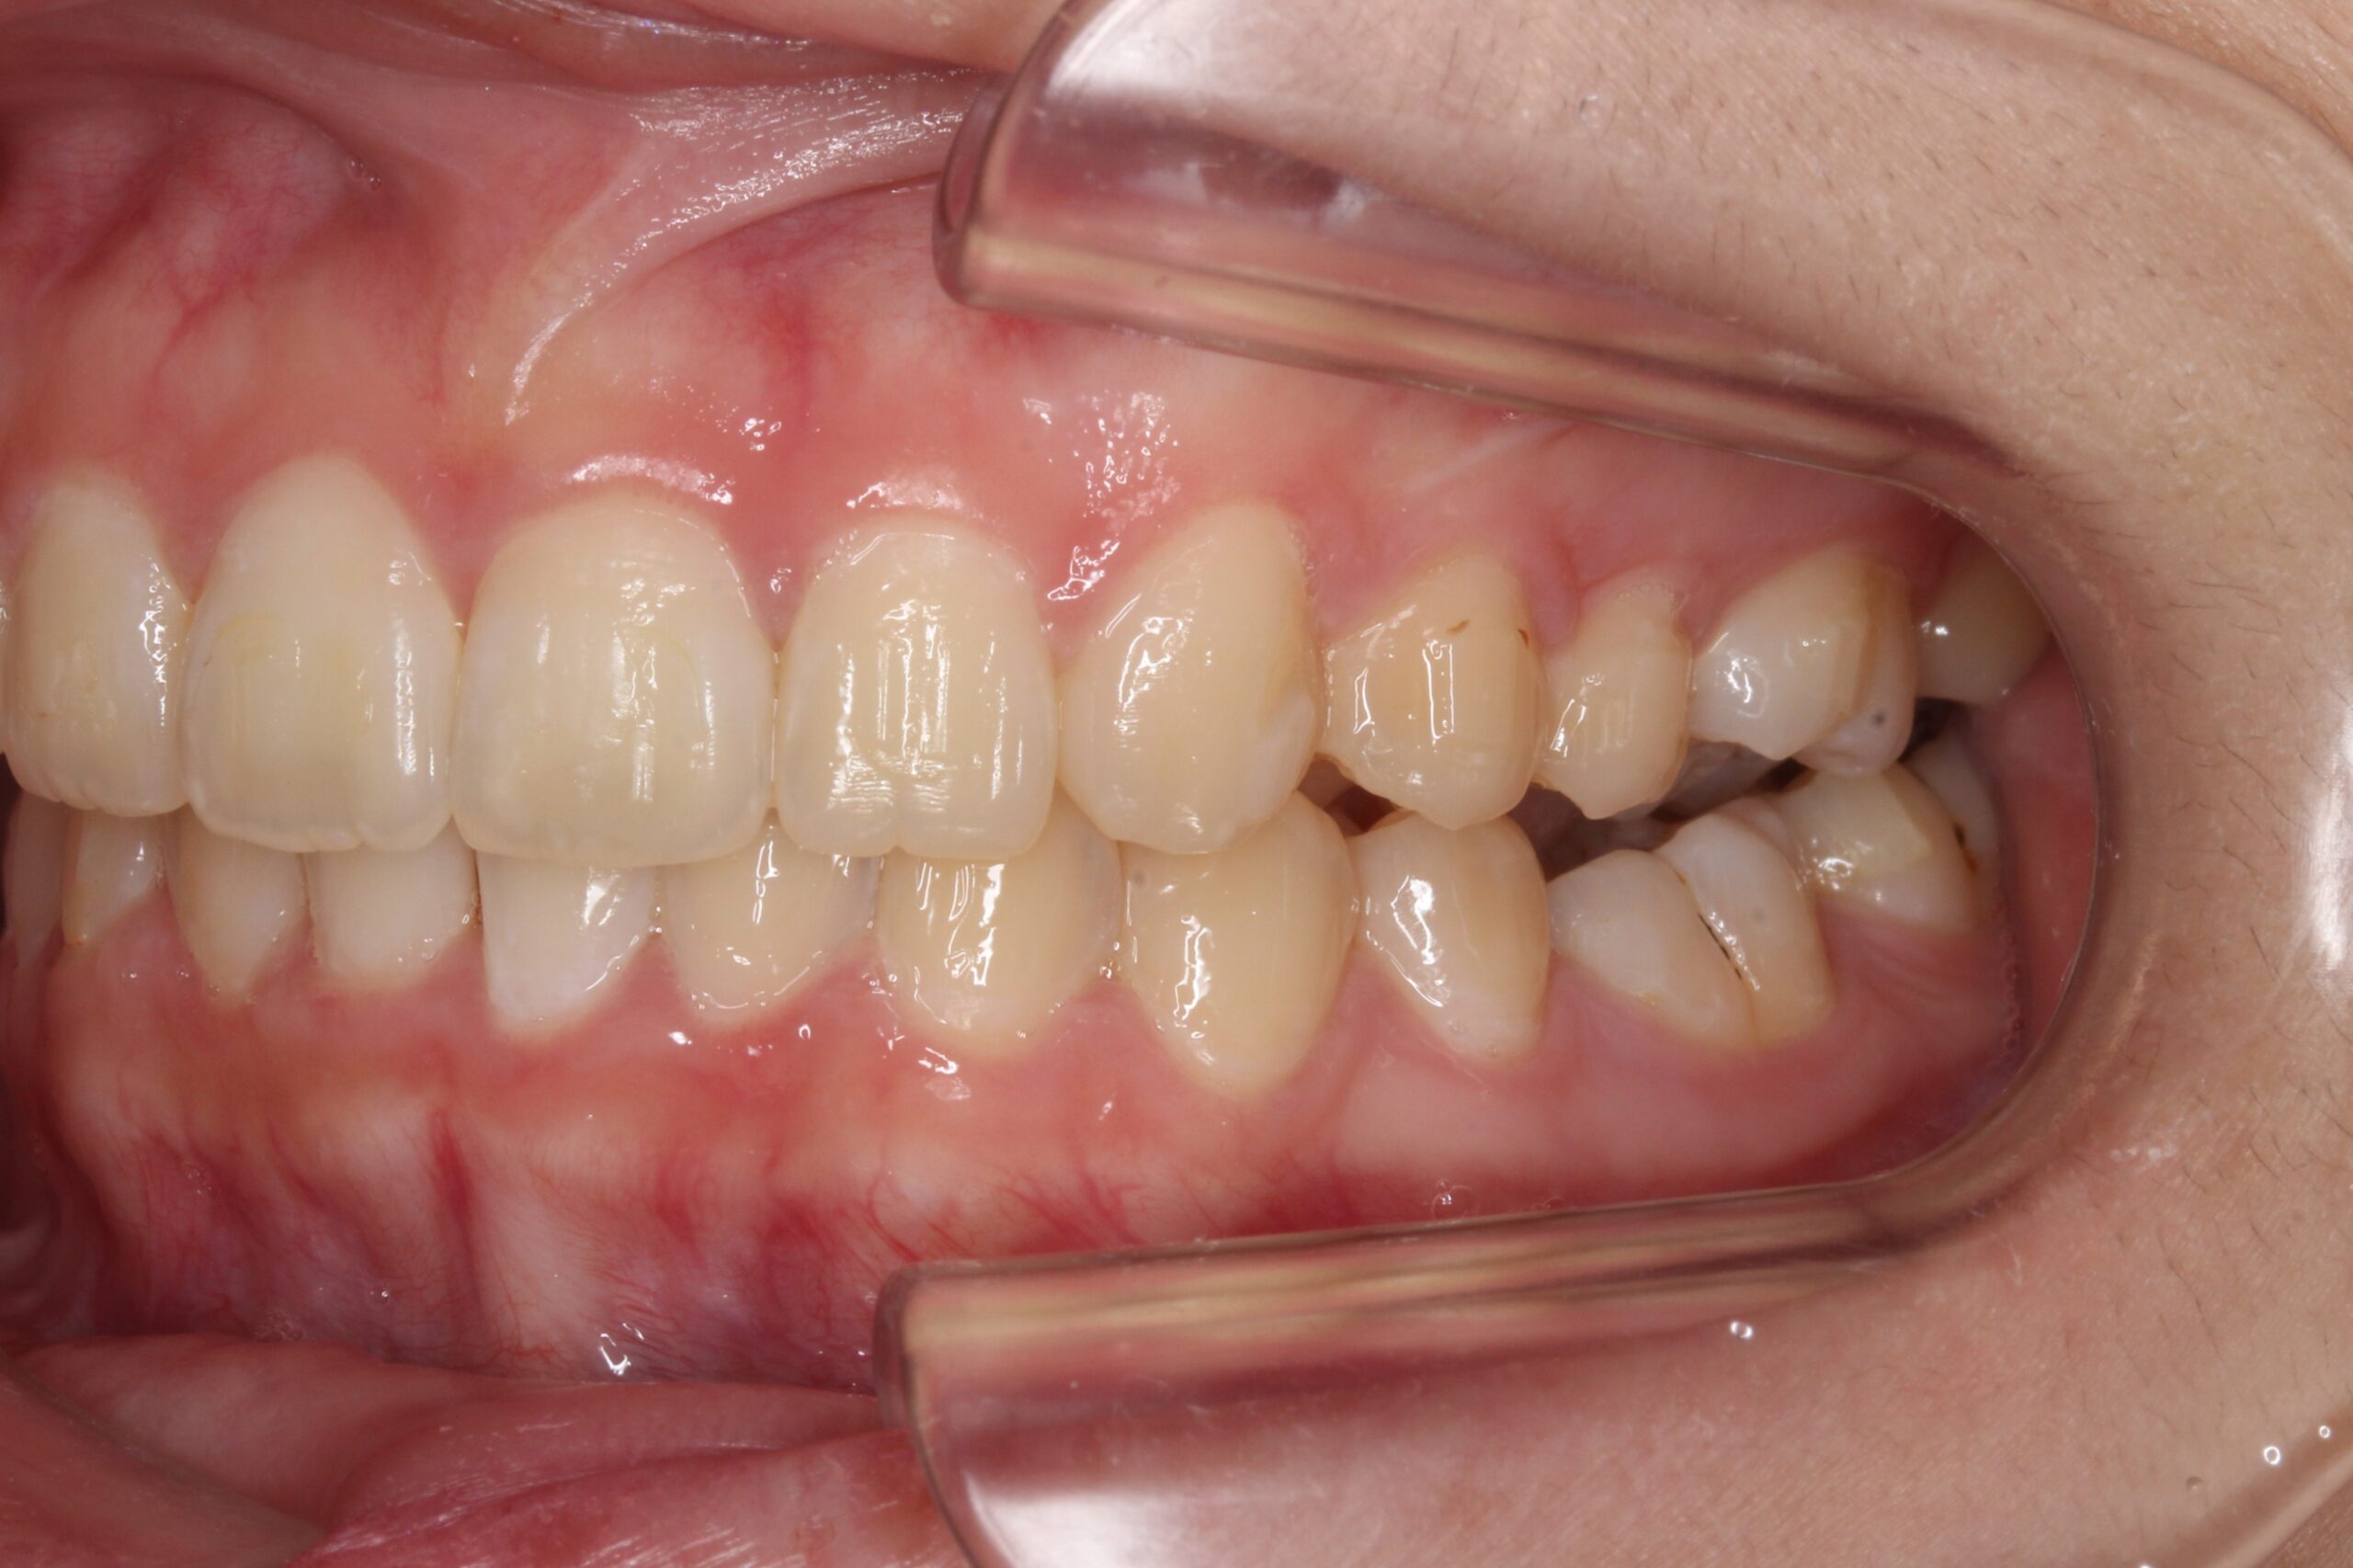

矯正術前:左側

矯正術後:左側